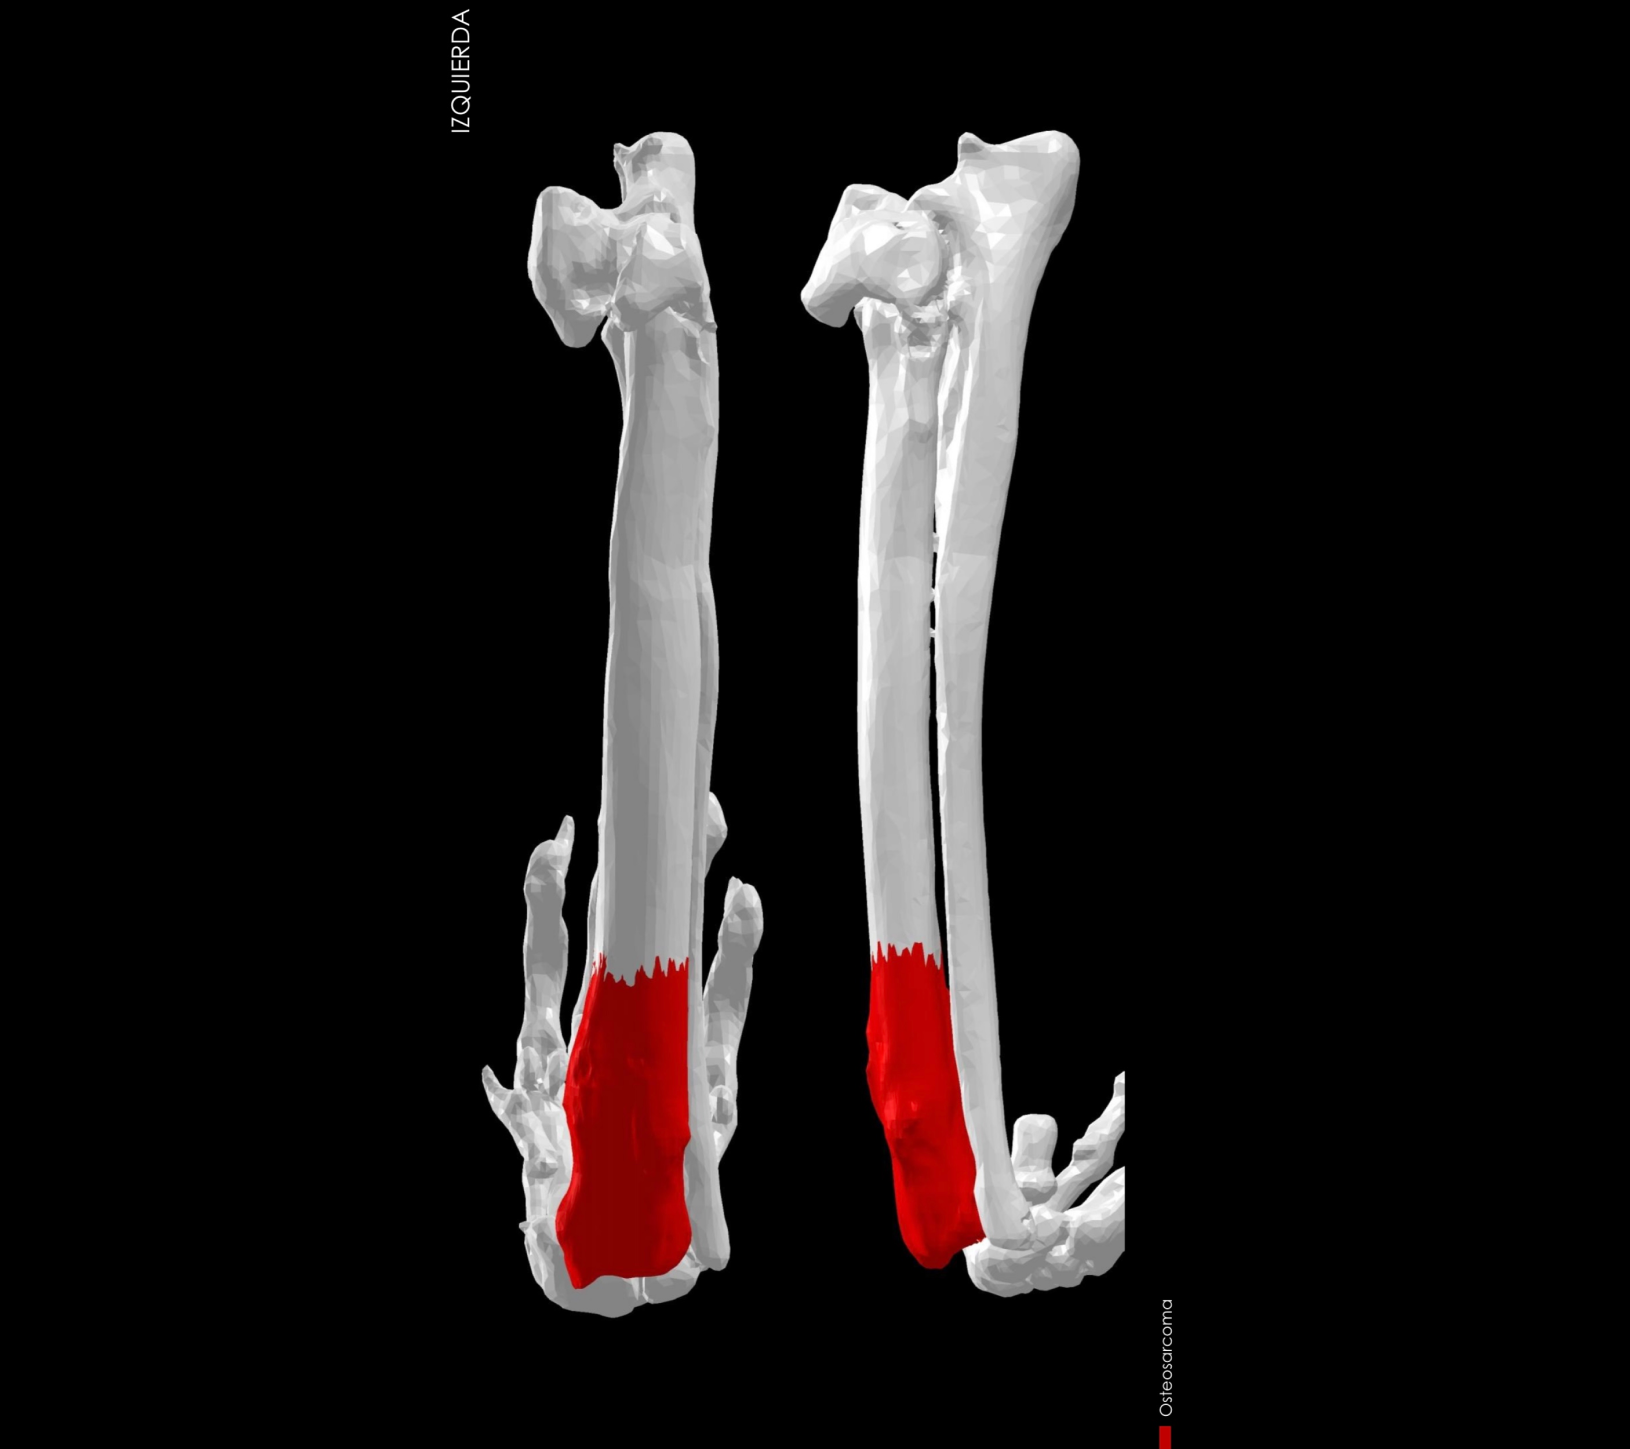

Su aplicación principal es en pacientes con neoplasias (tumores) óseas, como es en la mayoría de casos el osteosarcoma. Ante esta situación tradicionalmente era necesario llevar a cabo una amputación radical del miembro afectado. Actualmente gracias a técnicas de salvación de miembro, siempre y cuando el estado de salud general del paciente lo permita, es posible la resección quirúrgica del tumor y la reconstrucción de la extremidad afectada empleando diferentes prótesis anatómicas que ayudarán a restaurar la estructura y la función del miembro afectado.